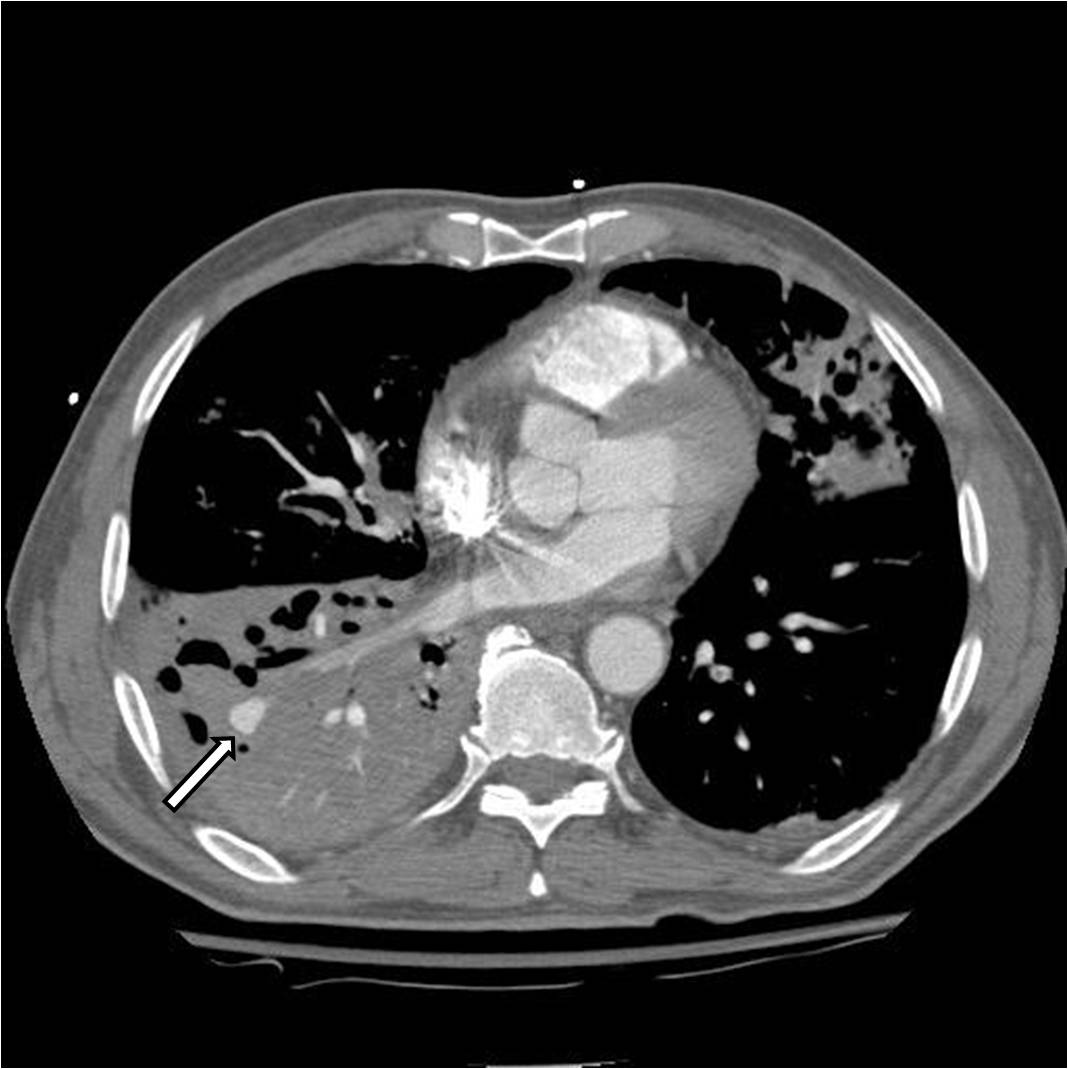

Figures